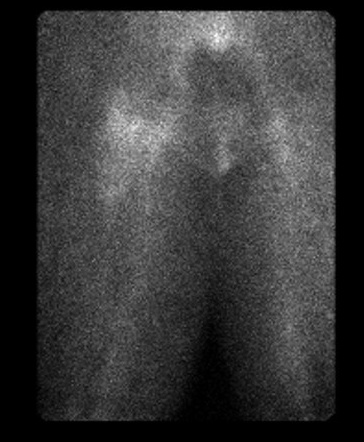

1. Three Phase Bone Scan

- low specificity for infection

- normal study likely excludes infection

- Cemented THA - majority return to normal by 1 year but 10% can remain positive past 1 year

- Uncemented THA - can remain positive for 2 years or longer

- infection - increased blood flow / blood pool / delayed phase

Quiescent bone scan